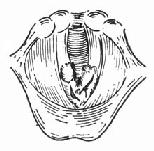

4.手术方法 ①颈部低位横切口行常规气管切开术(图96-10)。②常规喉裂开术(图96-11)。直视下仔细缝合喉粘膜裂口(96-12)。置入事先准备好的喉扩张模(牙模胶或硅橡胶制成)放入喉腔,扩张模下界在环状软骨水平,上界在室带水平即可,用金属线固定此扩张模。金属线穿过甲状软骨板和皮肤后,用钮扣固定在颈部皮肤表面(图96-13)。尽量对合复位甲状软骨板,并缝合甲状软骨板外软骨膜,逐层缝合切口(图96-14)。③手术后使用强有力的抗生素控制感染。按气管切开术后护理。④6~12周后直接喉镜下取出喉扩张模。⑤取模后试行堵管,无呼吸困难后可拔除气管套管。

图96-13 置入扩张模并固定之